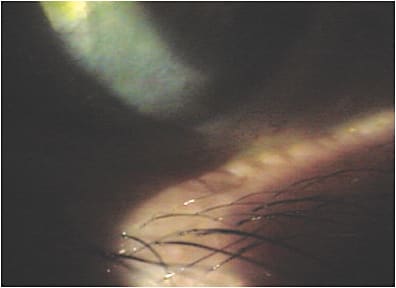

Blepharitis often contributes to ocular surface inflammation and can be a vexing disease to manage, as it sometimes becomes chronic and recurrent. Staphylococcus species are most commonly associated with blepharitis, although the presence of collarettes, or cylindrical dandruff, are a sign of demodex, a microscopic mite that can cause or contribute to blepharitis. - MGD. Previously described as posterior blepharitis, MGD specifically describes dysfunction, inflammation and often partial and sometimes complete loss of the meibomian glands.

- Blepharitis. This describes inflammation of the anterior lid margin marked by red, swollen eyelids, dandruff-like scurf, erythema, lash loss, crusting and matting with lid debris. Bacterial biofilm formation is also common.